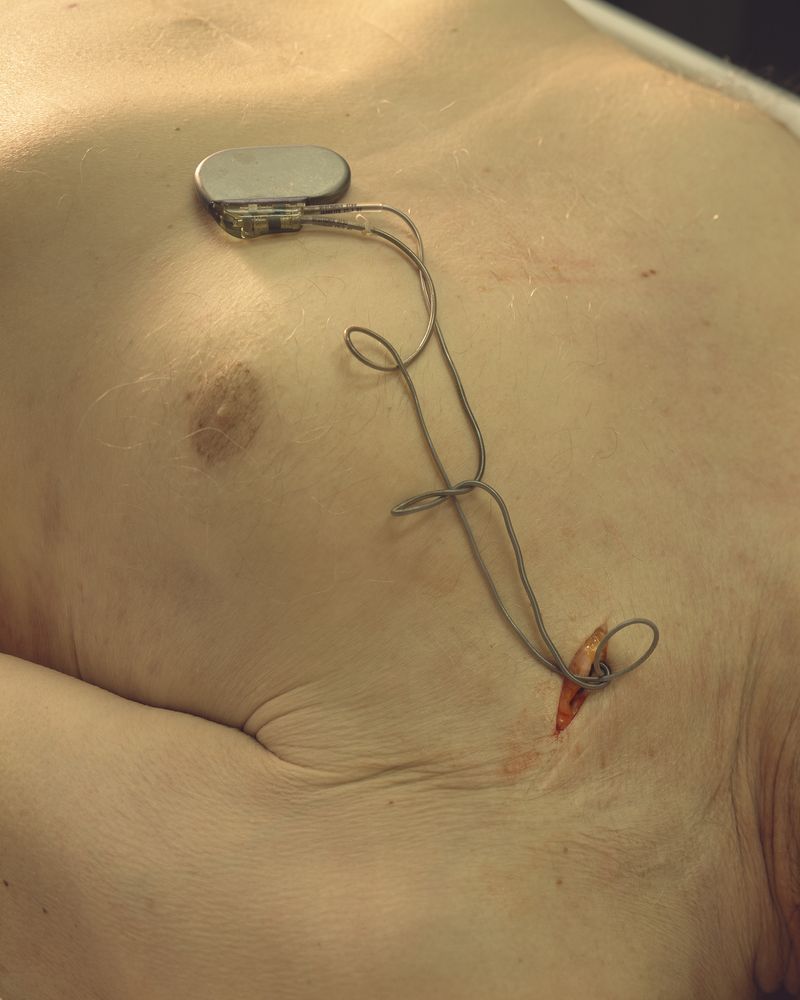

My work asks questions and challenges contemporary social and cultural attitudes towards the perception of death, the quality of life, reflections on the essence of humanity on philosophical and technological grounds. The story of our corporeality aims to begin a discourse about what has been tabooed or is socially marginalized:

medical bioengineering, technology in medical service, change in the perception of a dead body and the aspect of loss. Such a discourse could reveal the needs and solutions for the development of bioengineering in Poland. The increasingly appearing idea of transhumanism in this aspect considers dysfunctional elements of the human condition, such as disability, suffering, disease and ageing, to be undesirable, often still remaining only an idea but also a goal.